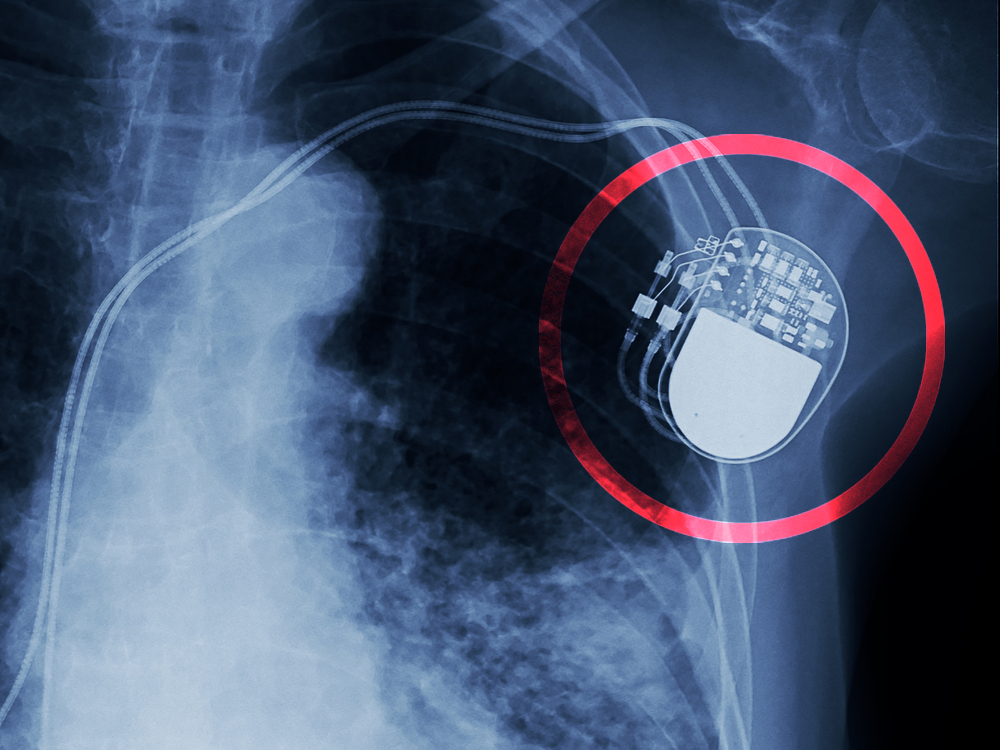

Πρόκειται για συσκευές ή τεχνητά εμφυτεύματα, όπως βηματοδότες, τεχνητά οστά (όπως ισχία), αντισυλληπτικά εμφυτεύματα, πλέγματα που χρησιμοποιούνται στη χειρουργική ή ακόμη και εμφυτεύματα για το στήθος.

– Ελαττωματικοί βηματοδότες είχαν προβλήματα τα οποία ήταν γνωστά στους κατασκευαστές.